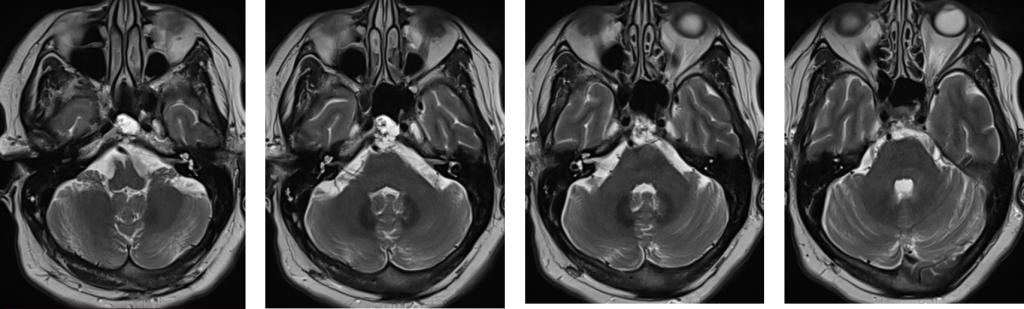

Figura 1: examinare IRM axial T2 se observă modificare de structură a clivusului cu prezența unor plaje cu semnal lichidian și de incluzii în hipersemnal T2 și FLAIR, hiposemnal T2 cu depășire posterioară a corticalei osoase.